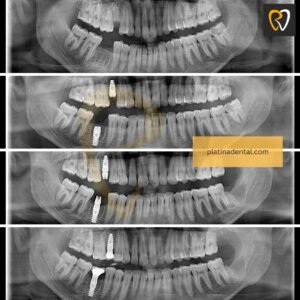

Missing Tooth Treatment in Hyderabad

Missing a tooth can lead to bone shrinkage and bite imbalance. We offer permanent missing tooth treatment in Kondapur Kukatpally using advanced dental implant systems for long-term stability.